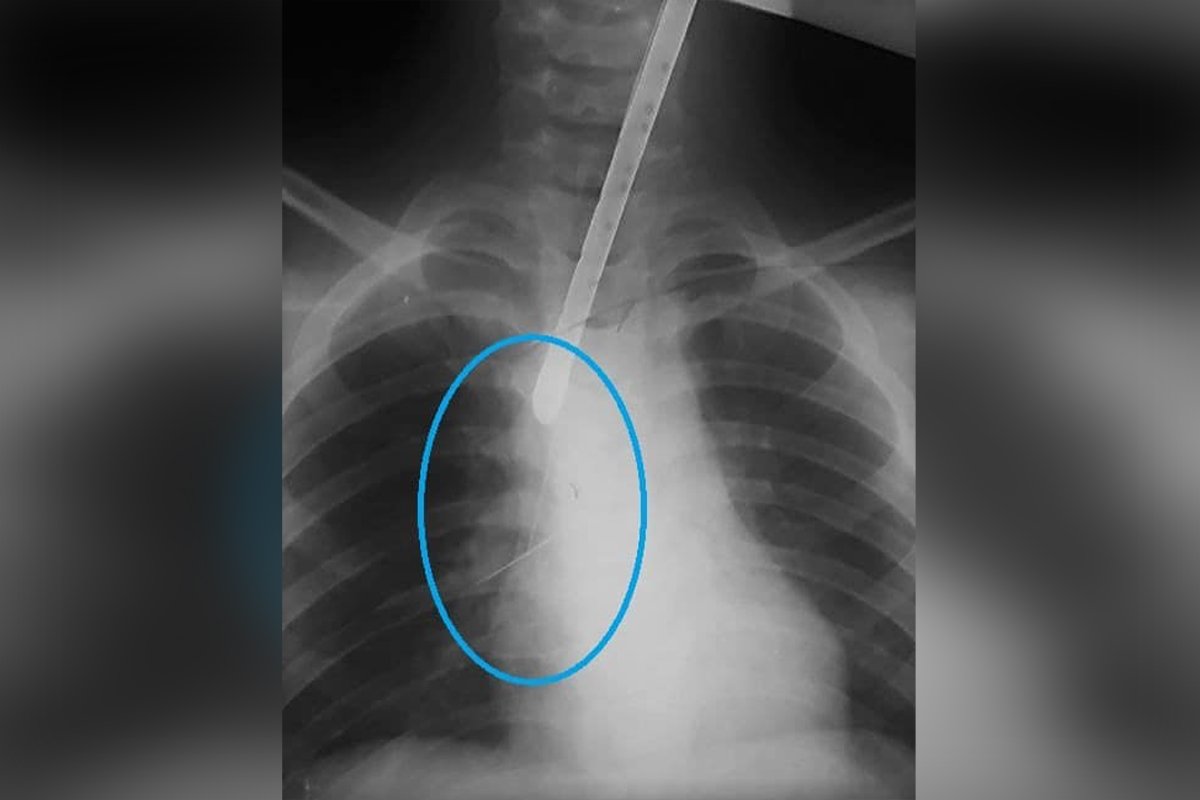

После эндоскопического исследования медики обнаружили портняжную булавку, которая подкололась к трахее. При попытке удалить предмет с помощью специальной петли инородное тело начало мигрировать вниз по дыхательным путям к правому, меньшему по диаметру, бронху. Ситуацию усложняло и то, что булавка спускалась головкой вниз, подкалываясь к сегментарному бронху. Малейшая неосторожность могла привести к осложнениям в виде травмы бронха или кровотечения. Поэтому специалистам пришлось искать нестандартное решение ситуации.